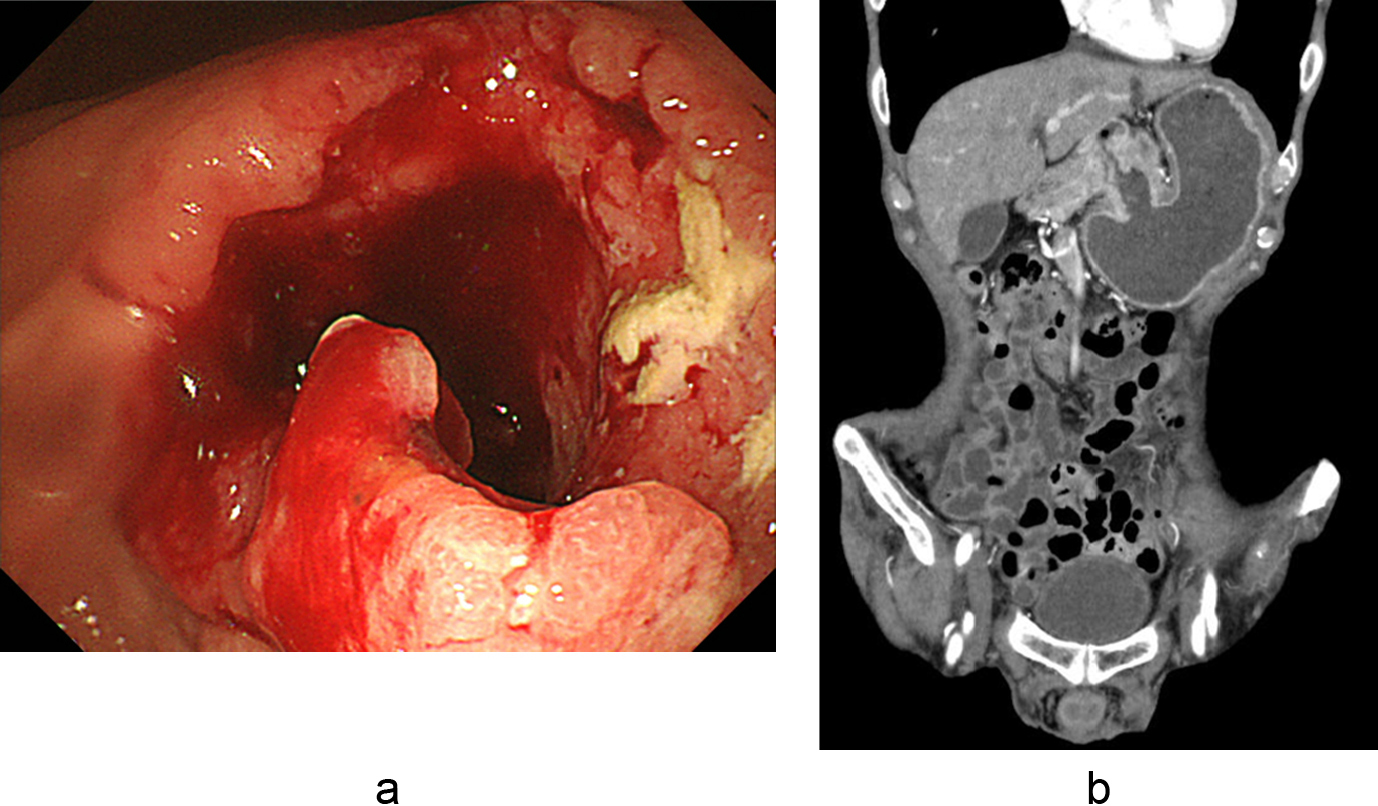

7. 内視鏡検査所見(図1a)前庭部にびまん浸潤型の腫瘍と全周性の狭窄を認めた.

7. 内視鏡検査所見(図5a)幽門前庭部から十二指腸球部にかけて全周性に潰瘍浸潤型の腫瘍を認めた.

胃前庭部に全周性の不正な壁肥厚と胃拡張を認めた.